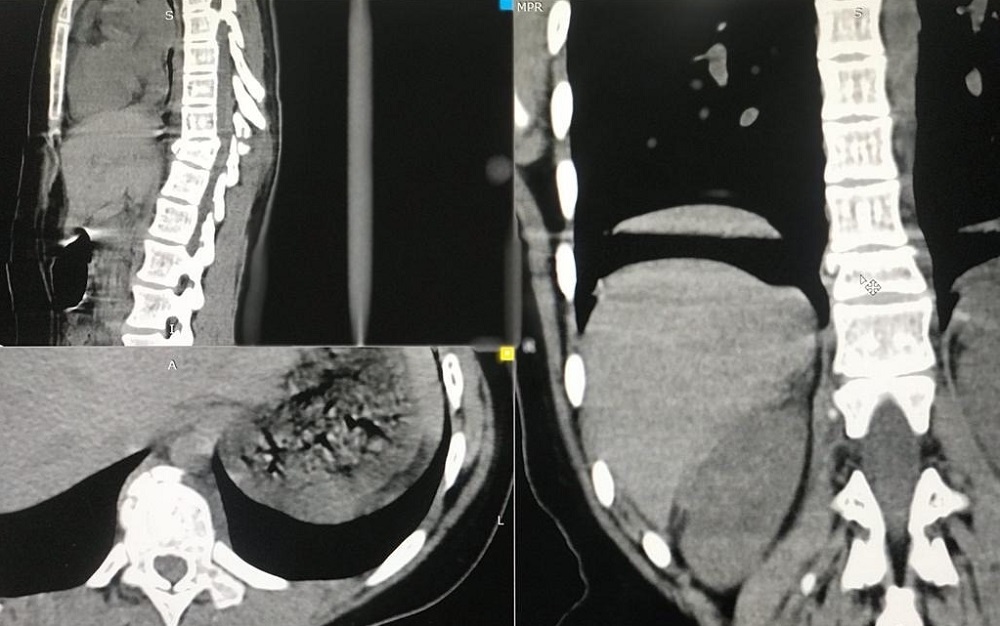

4 мая хирурги-травматологи Областной детской клинической больницы провели сложную трёхчасовую операцию на позвоночнике ребёнка и установили специальную фиксирующую конструкцию.

В последних числах апреля девочка каталась с друзьями на качелях и упала. Врачи диагностировали перелом позвоночника с деформацией и ушибы внутренних органов.

Было принято решение о проведении операции под полным рентген-контролем. Оперативное вмешательство выполнили Дмитрий Казюлин и Иван Четвериков, за рентген-аппаратом работал Олег Игнатов.

12 мая девочку выписали. Прогнозы врачей пока очень осторожные.